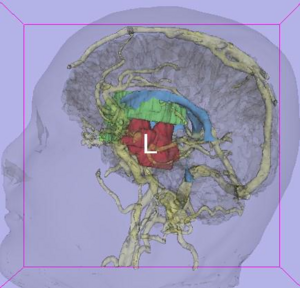

Publication: J Neurosurg. 2016 Jan 1:1-8. PMID: 26722859 Authors: Song F, Hou Y, Sun G, Chen X, Xu B, Huang JH, Zhang J. Institution: Department of Neurosurgery, People's Liberation Army General Hospital, Beijing, China. Background/Purpose: OBJECTIVE Preoperative determination of the facial nerve (FN) course is essential to preserving its function. Neither regular preoperative imaging examination nor intraoperative electrophysiological monitoring is able to determine the exact position of the FN. The diffusion tensor imaging-based fiber tracking (DTI-FT) technique has been widely used for the preoperative noninvasive visualization of the neural fasciculus in the white matter of brain. However, further studies are required to establish its role in the preoperative visualization of the FN in acoustic neuroma surgery. The object of this study is to evaluate the feasibility of using DTI-FT to visualize the FN. Methods Data from 15 patients with acoustic neuromas were collected using 3-T MRI. The visualized FN course and its position relative to the tumors were determined using DTI-FT with 3D Slicer software. The preoperative visualization results of FN tracking were verified using microscopic observation and electrophysiological monitoring during microsurgery. Results Preoperative visualization of the FN using DTI-FT was observed in 93.3% of the patients. However, in 92.9% of the patients, the FN visualization results were consistent with the actual surgery. CONCLUSIONS DTI-FT, in combination with intraoperative FN electrophysiological monitoring, demonstrated improved FN preservation in patients with acoustic neuroma. FN visualization mainly included the facial-vestibular nerve complex of the FN and vestibular nerve. |